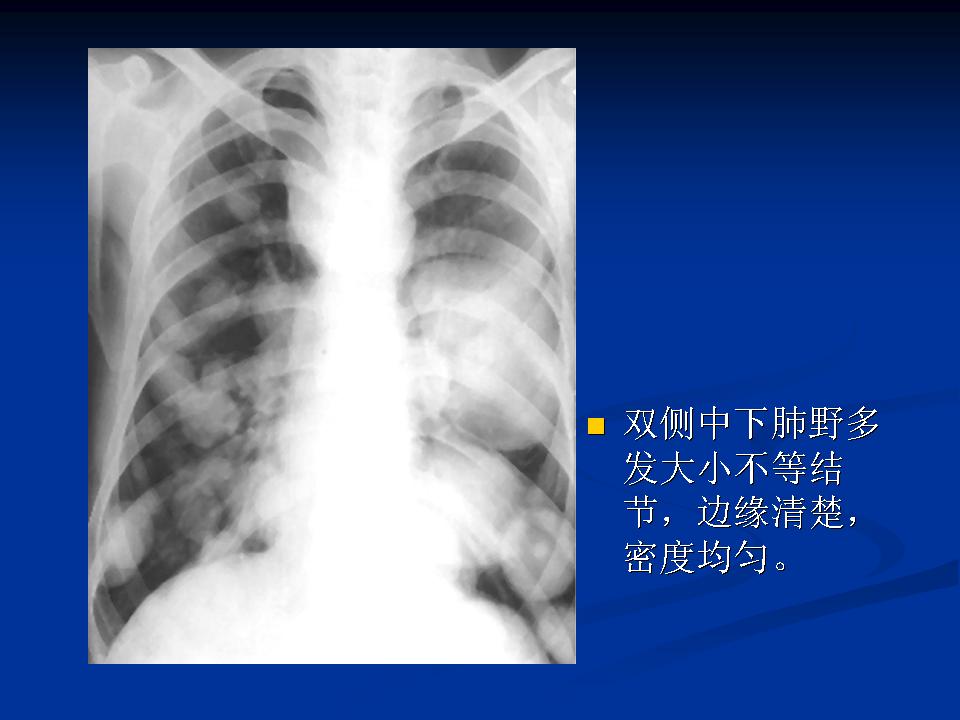

肺转移瘤与韦格肉芽肿影像鉴别